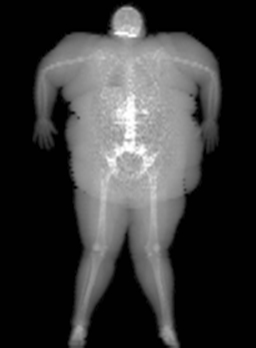

- Dynamic Filtration automatically adjusts the radiation dose based on tissue thickness, eliminating issues associated with saturation or starvation.

- Norland's unique Dynamic Filtration process ensures minimal subject radiation dose by adjusting X-ray flux based on tissue thickness.